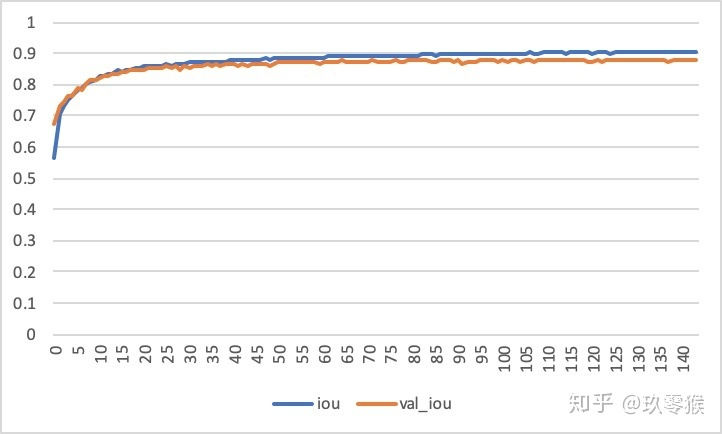

每一次epoch训练结束,都会对验证集进行测试Iou指标,如果比之前最好的还要好就保存本次训练模型,如果超过args.early_stop这个参数还没有训练更好的话,便结束训练,这个原理就是early_stop,主要还是防止网络训练过度,造成过拟合现象,这也就是验证集虽然没有直接参与训练,但是却在其中扮演了一个非常重要的角色!

运行的结果: